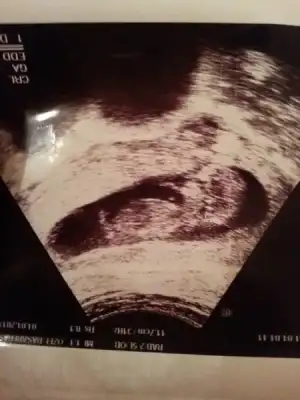

kızlar birde bize bakarmısınız ben anlayamadım şu nub teorisini![]()

Eki Görüntüle 1047942

Eki Görüntüle 1047943